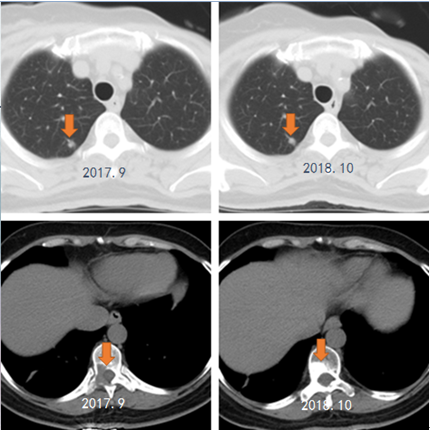

(1)肺部占位较前稍缩小( 2016.12-2017.9 )。

(2)胸椎第10椎体骨破坏( 2017.9 )。